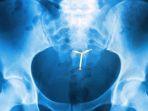

Wanita ini Tak Sadar Ada Benda di Rahimnya selama 29 Tahun, Pantas Tak Kunjung Hamil: Saya Kelelahan

Seorang wanita tak sadar bahwa ada satu benda yang tertinggal di rahimnya. Parahnya, benda itu bersemayam selama 29 tahun.